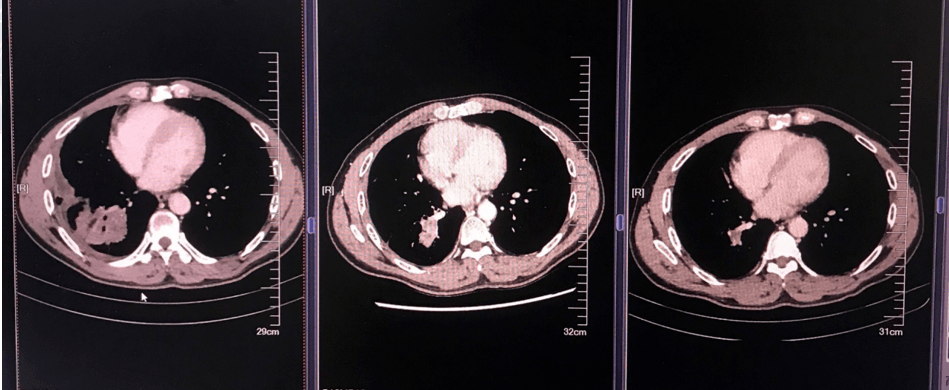

肺腺癌晚期肿瘤图片

图片尺寸666x500